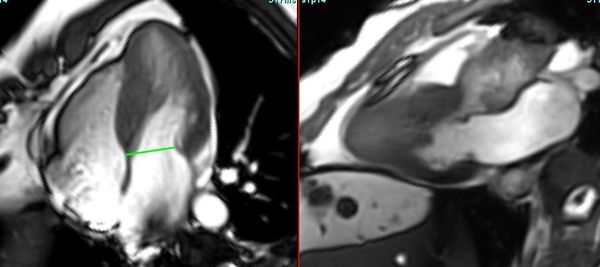

A subendocardial membrane is a distinctive sign of this condition

A large heart in a young mother